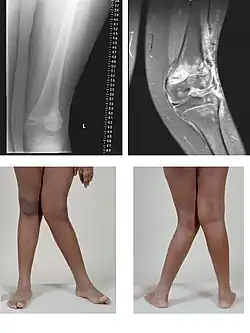

In der Ansicht von vorn auf die Frontalebene erscheint eine Achsfehlstellung bei gestrecktem Bein als O-Bein oder Genu varum, wenn der Unterschenkel im Vergleich zur Oberschenkelachse nach innen abweicht (Varusstellung), beziehungsweise als X-Bein oder Genu valgum, wenn der Unterschenkel im Vergleich zur Oberschenkelachse nach außen abweicht (Valgusstellung). Die Folge ist jeweils eine einseitige Mehrbelastung des Kniegelenks.

Bei der Normalstellung liegt der Mittelpunkt des Kniegelenks genau auf der Linie zwischen dem Mittelpunkt des Hüftgelenks und des Sprunggelenks (Mikulicz-Linie). Der außenseitig gemessene Winkel zwischen den Schaftachsen des Oberschenkels und des Unterschenkels beträgt ca. 174°.[1]

- Eine O-Bein-Stellung (ein Genu varum) liegt bei einem deutlich größeren Winkel (ab ca. 180°[1]) vor (lat. varus = „auswärts gebogen, krummbeinig“).[2] Dann liegt das Knie weitgehend außerhalb der Mikulicz-Linie, siehe auch Varusstellung.

- Eine X-Bein-Stellung (ein Genu valgum) liegt bei einem deutlich kleineren Winkel (ab ca. 171°[1]) vor (lat. valgus = „säbelbeinig“).[3] In diesem Fall liegt das Knie deutlich weiter innenseitig der Mikulicz-Linie, siehe auch Valgusstellung.

Meistens haben beide Kniegelenke dieselbe Fehlstellung. Wenn man beide Beine zusammen betrachtet, ergibt sich das Bild eines O bzw. eines X. Die Bezeichnungen O-Beine und X-Beine werden daher vorzugsweise im Plural verwendet.[4]